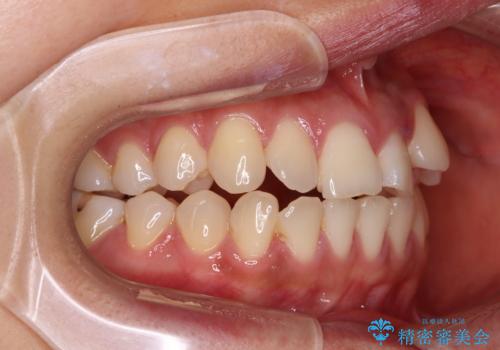

- 左上の前歯のがたつきを主訴に来院された患者様です。

上顎歯列が下顎の歯列に対して狭小であり、一部下顎の奥歯が上顎よりも外側に位置している状態でした。

上顎の歯列を拡大しスペースを設け、さらに左上の小臼歯を一本抜歯し左上の八重歯を歯列内に入れ整えていくことにしました。